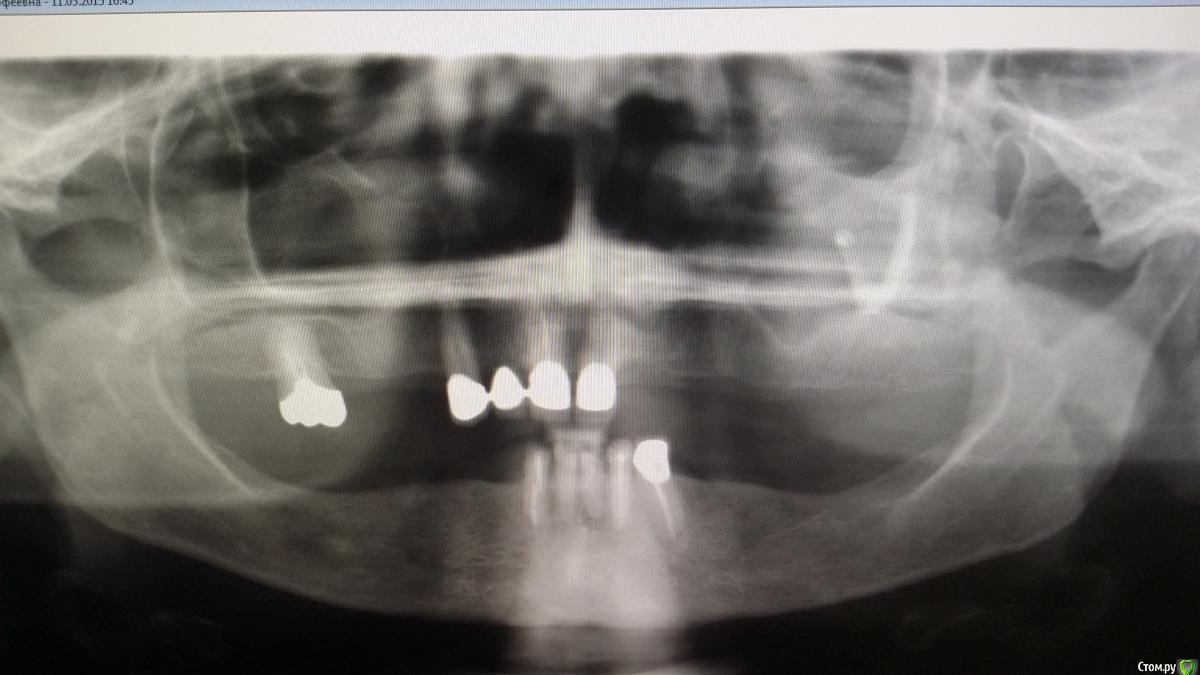

Recive Опубликовано 14 мая, 2015 Поделиться Опубликовано 14 мая, 2015 Пациентка лет 65-ти принесла ассорти своих протезов и попросила помочь. Рвотный рефлекс проверял обратной стороной зеркала, проводя по небу.что делать если вариант имплантации не рассматриваем.? Ссылка на комментарий

Magomed Опубликовано 16 мая, 2015 Поделиться Опубликовано 16 мая, 2015 терпеть или ставить имплант. вроде и по высоте всё ок Ссылка на комментарий

Saymon Опубликовано 17 мая, 2015 Поделиться Опубликовано 17 мая, 2015 Телескопов еще не хватает в коллекции. А так единственный вариант уйти от имплантации и снизить границы съемного протеза. Ссылка на комментарий

Nixon Опубликовано 17 мая, 2015 Поделиться Опубликовано 17 мая, 2015 Делайте телескопический протез с опорой на зубы.для изготовления протеза без перекрытия неба опорных зубов достаточно.Только нужно перелечивать опорные зубы и смотреть.что делать с живыми зубами Ссылка на комментарий

Recive Опубликовано 20 мая, 2015 Автор Поделиться Опубликовано 20 мая, 2015 (изменено) Делайте телескопический протез с опорой на зубы.для изготовления протеза без перекрытия неба опорных зубов достаточно.Только нужно перелечивать опорные зубы и смотреть.что делать с живыми зубами Телескопическая система фиксации? Вы не шутите?!Там очень добротная мкк стоитостановились с пациенткой на том, что делаем Acry free с её подписью что если будет тошнить то это её проблемы И большой вопрос что делать с низом. Там тоже телескопы? Изменено 20 мая, 2015 пользователем Recive Ссылка на комментарий